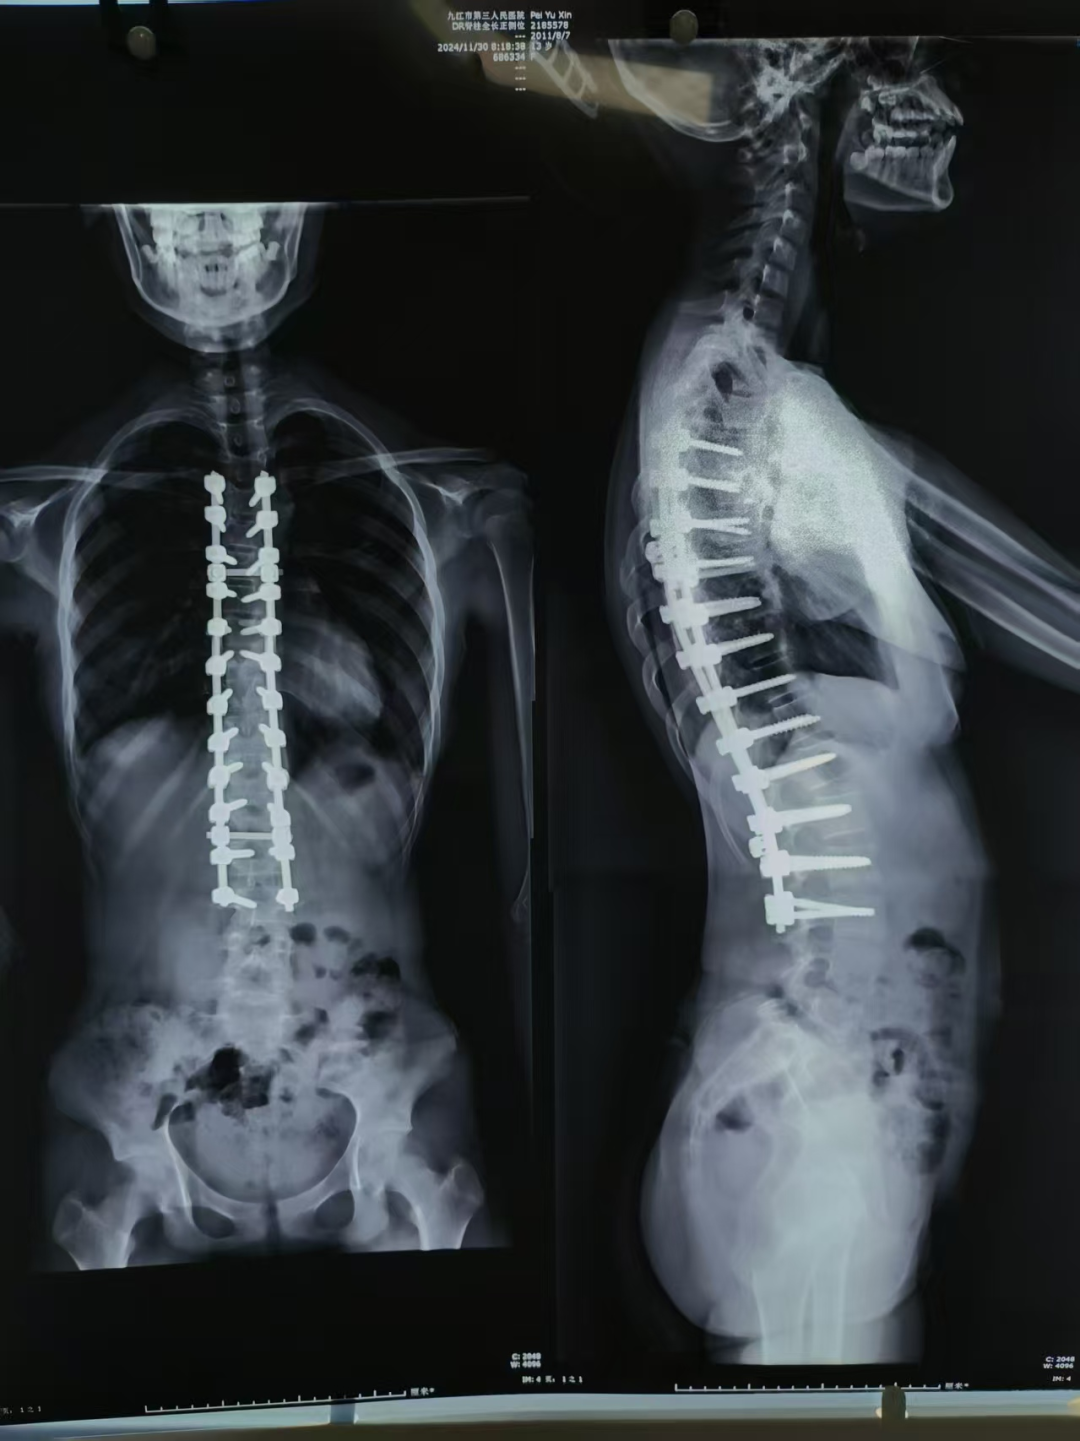

对于侧弯角度大于45°、进展迅速或支具治疗效果不佳的重症患者,脊柱外科承担手术治疗任务。科室采用后路脊柱融合内固定等现代术式,在神经电生理监测等技术保障下,安全、精准地矫正畸形重建脊柱平衡。术后贯彻快速康复理念,帮助患者尽早恢复功能。

图片